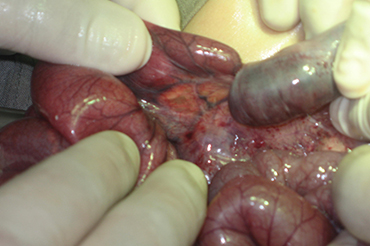

Invaginación Intestinal